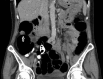

Schwannomas are peripheral nerve sheath tumours that can present as a rare tumour of GI tract, and even more uncommonly within the colon. We present a case of colonic schwannoma in an asymptomatic patient identified on surveillance colonoscopy. The tumour is of mesenchymal origin and is often challenging to diagnose prior to surgical resection. Endoscopy usually fails to provide adequate sample and diagnosis is usually confirmed on immunohistochemistry.